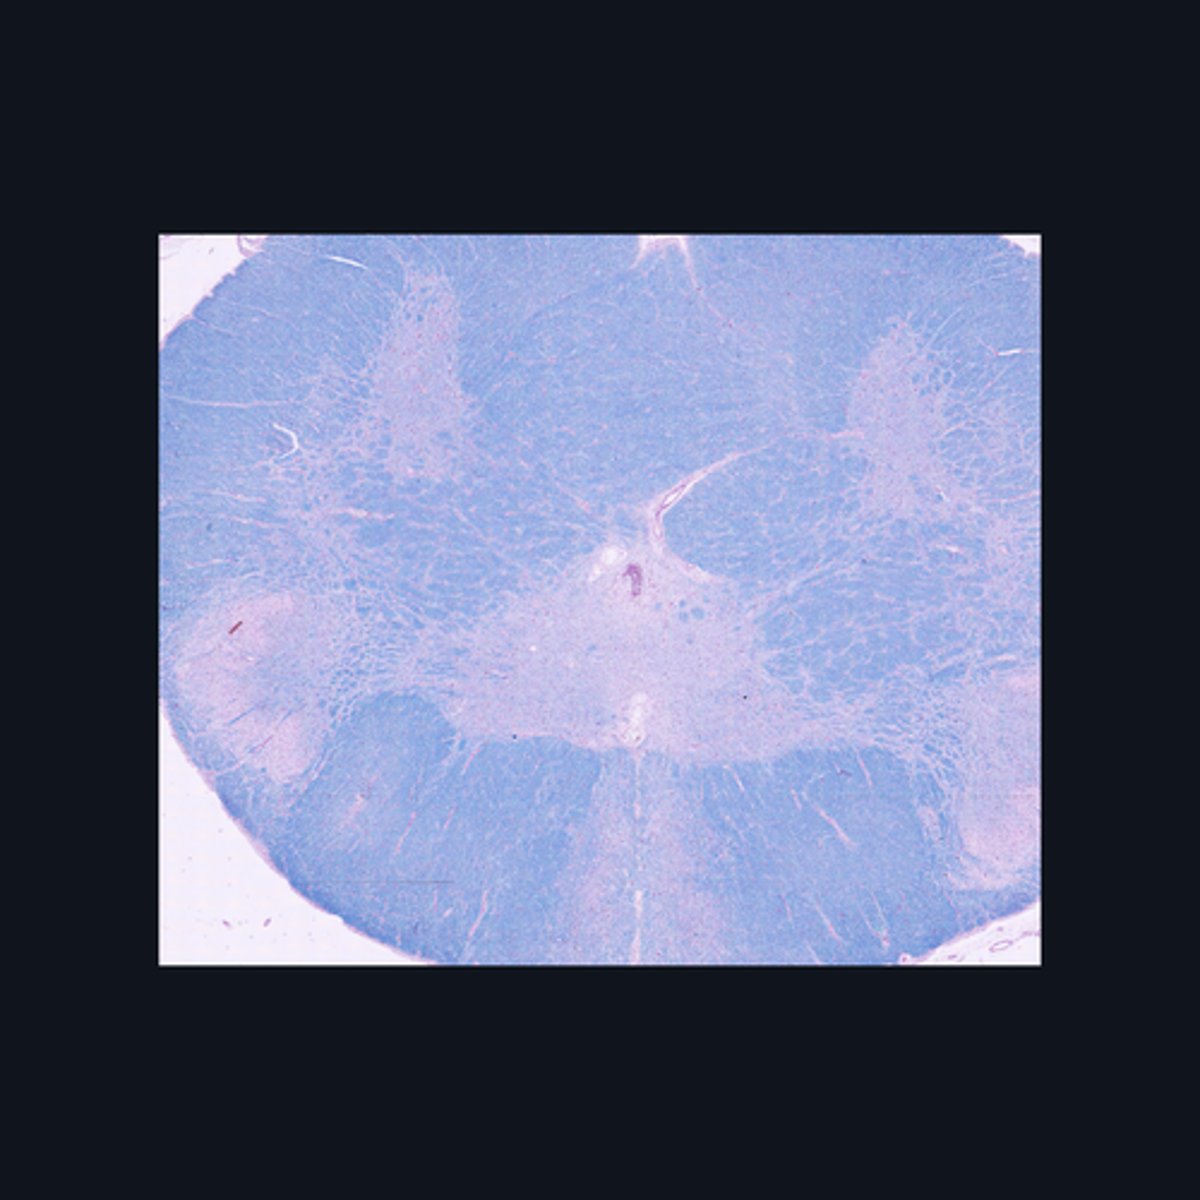

Sacral region

Identify the region of the spinal cord in the given image.

Identify the parts of the sacral region of the spinal cord.

FALSE

T or F: The white matter in this region of the spinal cord is larger than the white matter in the thoracic region of the spinal cord.